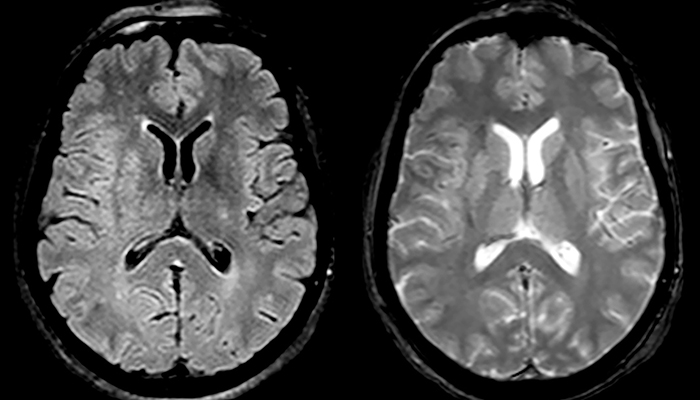

“Every center is different, but for me the ideal protocol for stroke includes diffusion weighted imaging, FLAIR, and fast susceptibility imaging,” says Dr. Savatovsky. “Our fast susceptibility weighted imaging takes 50 seconds, so it’s as fast as T2*-weighted imaging. It visualizes hemorrhage but also the clots. We also do 3D MR angiography that provides information on cervical and brain vessels. If the patient does not need immediate treatment, or if additional information is needed to decide on treatment, we might also add perfusion imaging and post-contrast T1-weighted imaging.”